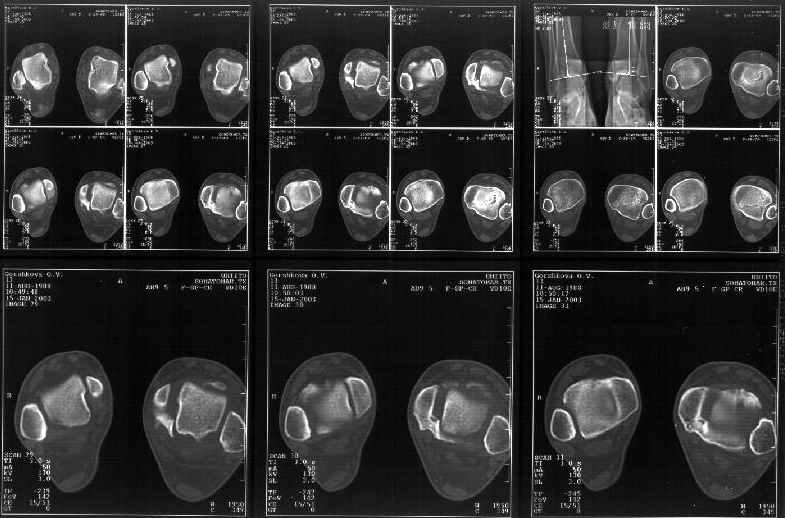

Сегодня пациентке сделали сравнительную КТ. А ксиальные и Фронтальные срезы приложены. Ваше мнение?

Фронтальные

Аксиальные

Спасибо за КТ -она изумительная. К сожалению, я по дороге на врачебный викенд на Мёртвом море и не смогу подготовить комментарий и схемку до 19.01.03 Помоему, результат КТ даёт чёткую возможность красивой и эффективной помощи.

На КТ я попытался изобразить скромными своими способностями (А)- место перелома, (С)- нормальный суставной зазор меж тараном и тремя его маллеолами. (В)- образовавшийся в результате перелома широкий раза в три зазор, позволяющий, по-моему, сублюксацию тарана при ходьбе. В свете данных КТ, критически важных, я бы предложил вертикальную остеотомию места перелома

задне-внутренним подходом и фиксацию мед. маллеола прижатым к тарану с помощью тонкого compression screw. После этого гипсовый сапожок и немедленное расхаживание ноги.